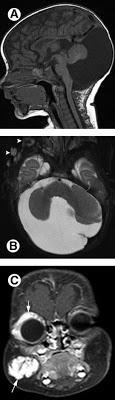

Sd PHACE. Dandy-Walker y hemangioma orbitario y facial

-Síndrome PHACE: poco frecuente, más habitual en niñas, con hemangioma segmentario en la cara, ,malformaciones de la fosa posterior craneal (ej Dandy-Walker), anomalías arteriales vasculares cerebrales, , coartación de aorta y otros defectos cardiacos, , anomalías oculares y anomalías de la línea medioesternal. el diagnóstico lo da un hemangioma facial segmentario unido a una alteración extracutánea.Fuera de los hemangiomas infantiles, tenemos los hemangiomas congénitos, que son hemangiomas que están ya en el parto. Hay que distinguirlos de raros tumores neonatales (fibrosarcoma congénito).Todos son negativos al GLUT-1, unos son de rápida involución y otros no (RICH y NICH). El hemangioendotelioma kaposiforme son diferentes neoplasias de distinto grado, con pronóstico que depende de su tamaño y localización. Suele asociar el famosos síndrome de Kasabach-Merrit, en el que existe un consumo de plaquetas y factores de la coagulación (que nunca se dará en un hemangioma infantil por muy grande que sea).El angiblastoma es otro tumor vascular que también puede crearlo, y no involuciona. EL granuloma piógeno es una pápula roja intesa, pediculada, que sangra con facilidad y progresa en poco tiempo, suele aparecer en zonas de traumatismos.

El 90% por la clínica y no tiene complicaciones ni se asocian a a otras patologías. Ahora, si existen dudas, o se quiere valorar la extensión o pueden existir malformaciones asociadas, puede usarse la ecografía doppler especialmente en hemangiomas lumbosacros, en niños con 5 ó más hemangiomas (eco hepática), en hemangiomas segmentarios faciales (eco cerebral). La resonancia magnética debe reservarse para casos concretos e individualizados (hemangiomas perineales extensos, hemangiomas de la vía aérea, atípicos, etc. Las pruebas endoscópicas, oftalmológicas etc se limitan a los casos raros en los que se complican o son de riesgo.